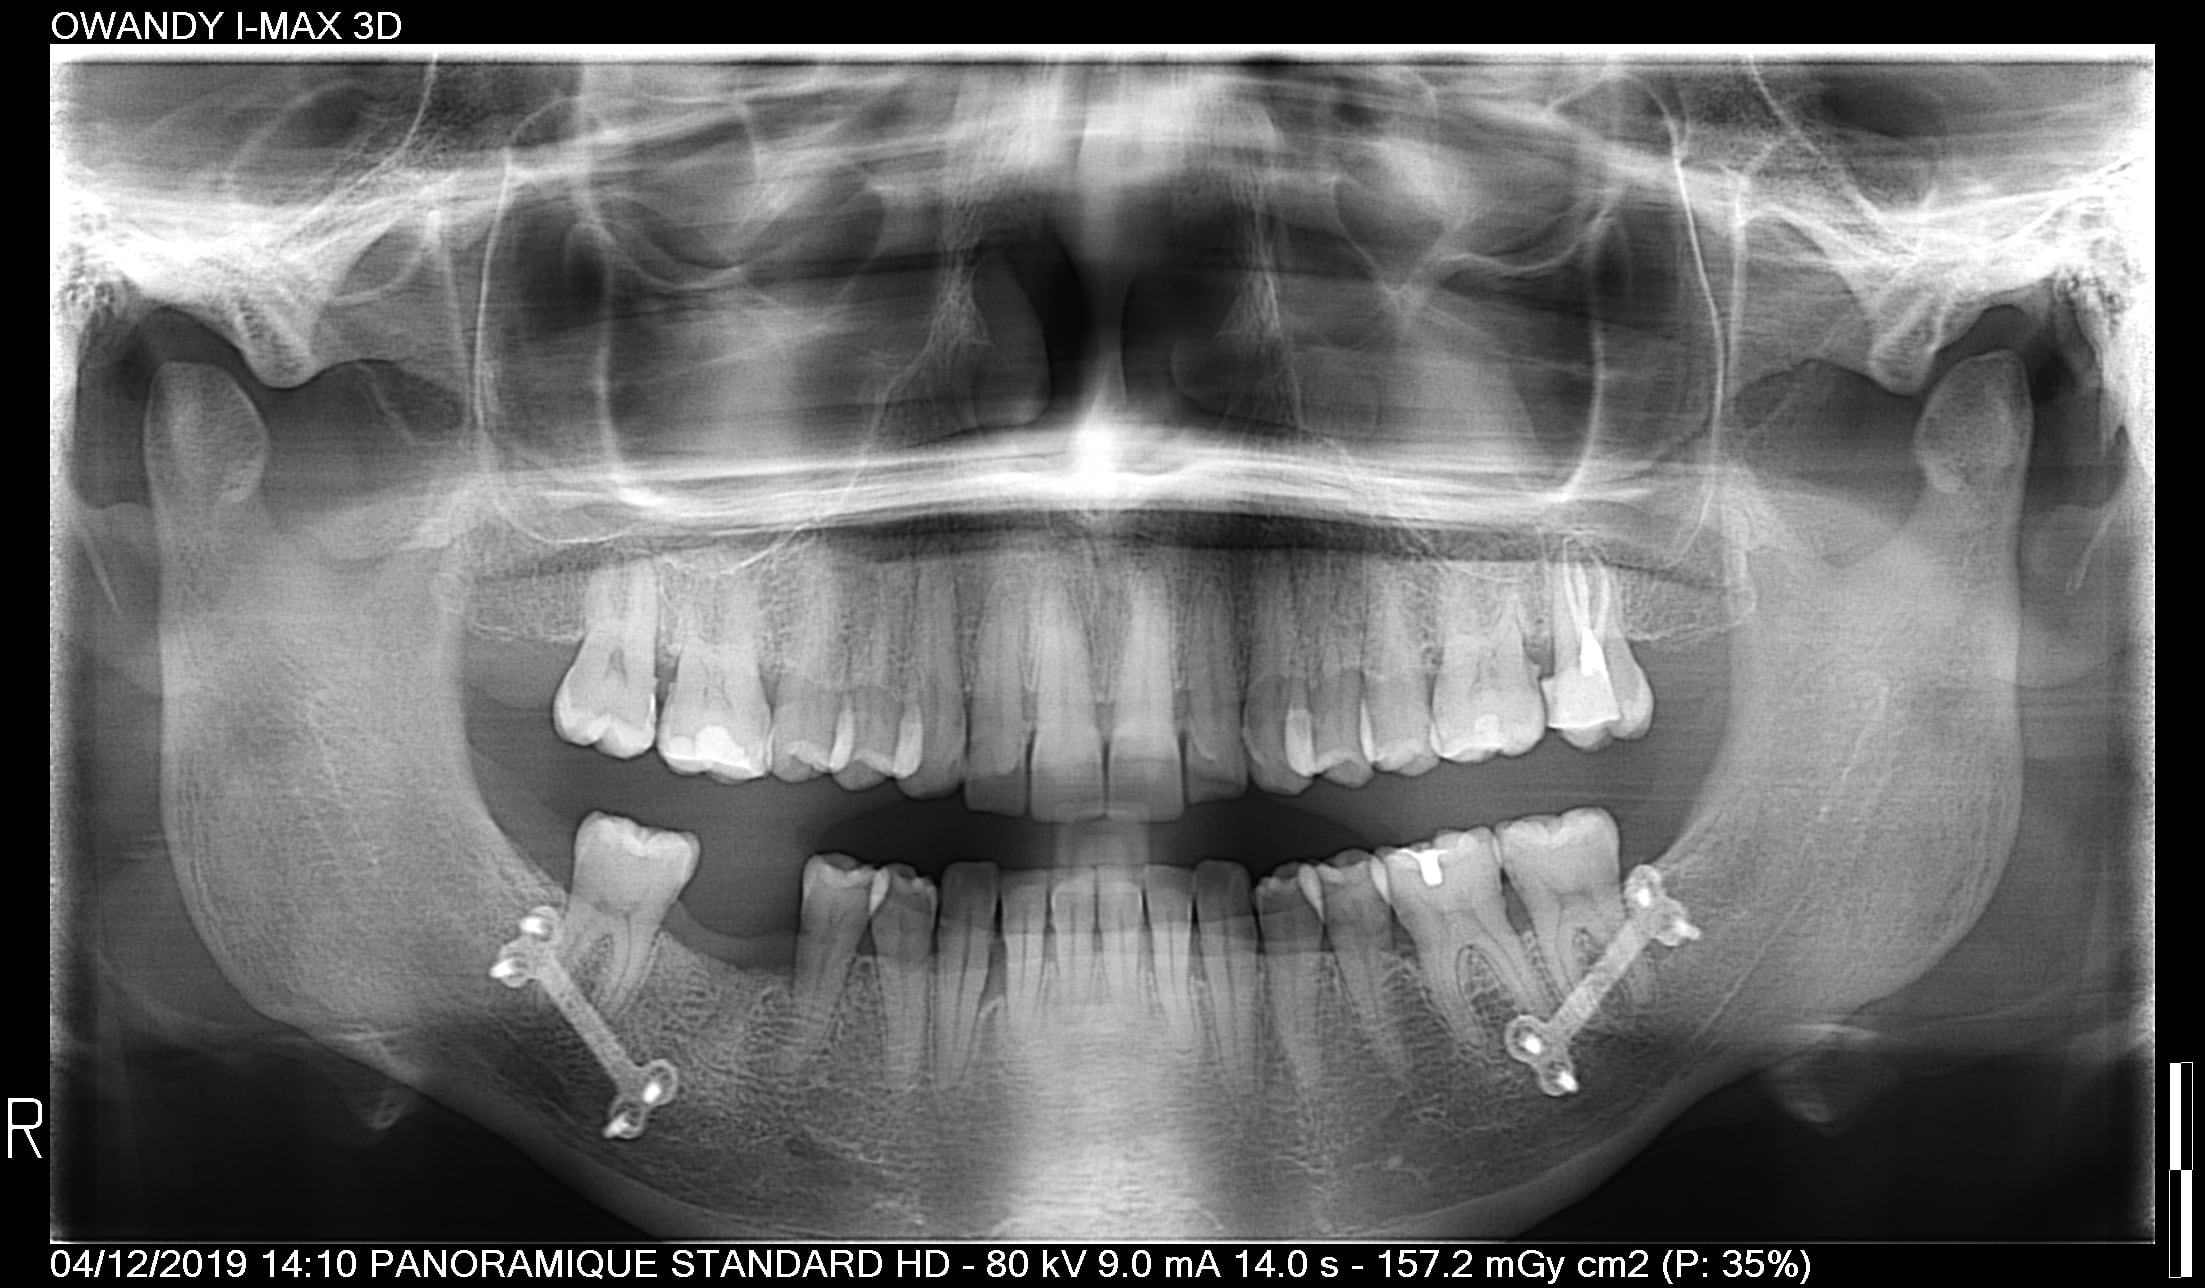

+ Site : ATCD de fracture mandibulaire consolidée - dent extraite suite carie/ LIPOE avant, curetage sans comblement attente 12 mois (Validation d'une stabilisation paro suite traitement non chirurgical/COVID19))

De sousa warda p001 2019.12.04 14.10 - Eugenol

A moins que j'aie mal lu, personne pour parler des plaques de fixation en titane.

Sont elles dues a un LEFORT III ou un accident (je pense plutot au premier cas, symétrie assez parfaite).

Hypothese: pendant longtemps on peut avoir un os assez peunspongieux, peu vascularisé en aval des plaques. Est ce que cette mobilité bizarre de la 7 qui normalement n'aurait pas du moufter (!) et le rejet implantaire ne sont pas dus a ca?

Elle a bien subit une osteotomie pour de l'orthognatique mais cela date de 1994 ...